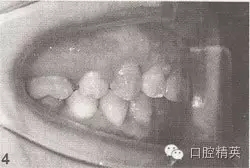

參見圖9-33 雙側(cè)后牙鎖頜矯治前后

A.雙側(cè)后牙鎖頜矯治前

B.雙側(cè)后牙鎖頜矯治后